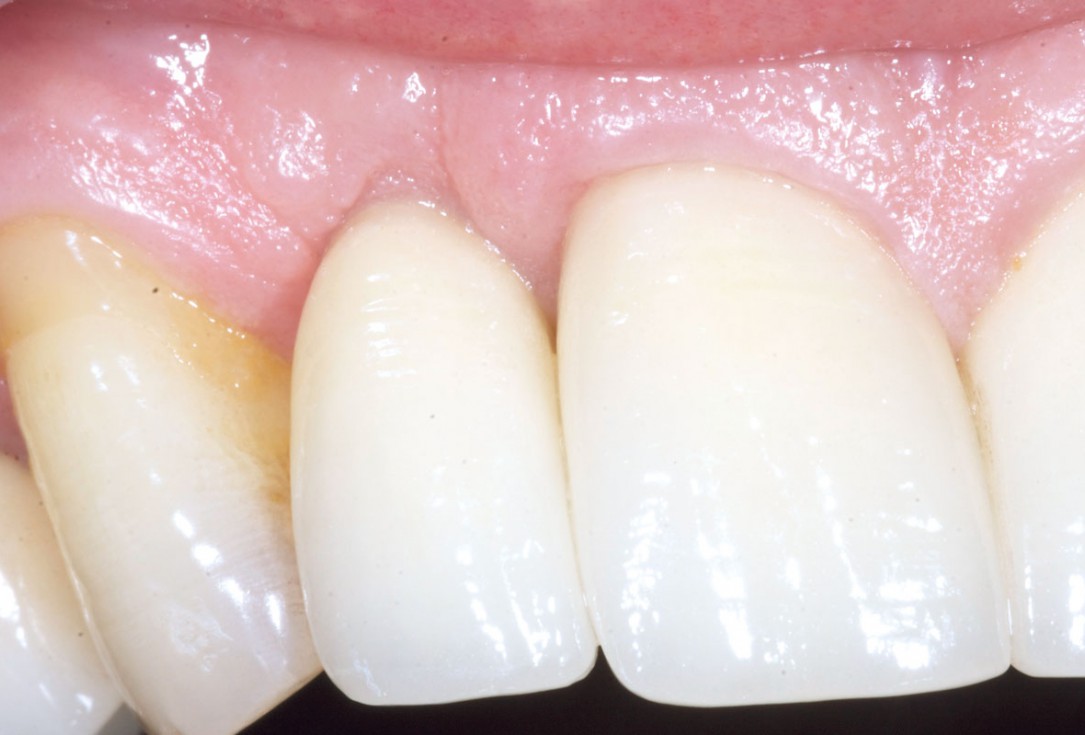

1/19 - Initial situation: Inflammated tooth #12Bone augementation with maxresorb® - Dr. R. Cutts